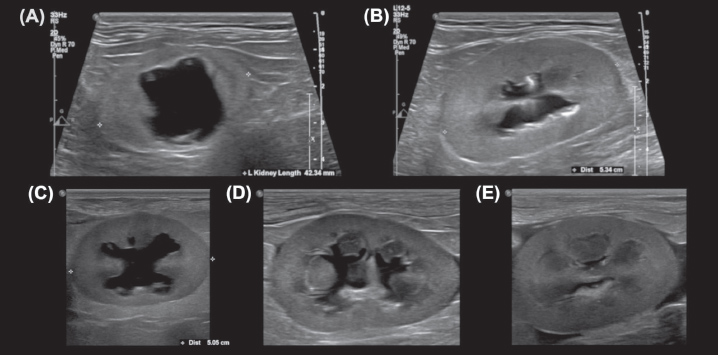

Overall, measurements from the sagittal plane performed worse than those from the dorsal and transverse planes, possibly due to the variable appearance of the renal pelvis in this plane; its margins may undulate, and it might be bisected by the renal crest depending on the level of insonation (Fig. 3). A study of murine kidneys proposed a hydronephrosis grading method that might mitigate the effects of this variation by calculating the percentage of renal height comprised of renal parenchyma (as opposed to renal pelvis) in the sagittal plane (Carpenter et al., 2012). Disappointingly, the interobserver variability of this method was found to be only ‘Moderate’ when applied to cats in our study (Fig. 4).

Fig. 3. Sagittal plane images of multiple kidneys, demonstrating the variable appearance of the renal pelvis. (A, C) The renal pelvis is not bisected by the renal crest. (B, E) The renal pelvis is completely bisected by the renal crest, which varies in thickness and margination between the images. (D) The renal crest incompletely bisects the renal pelvis, appearing as an amorphous echogenic structure in the center of the renal pelvis. Note the undulating margins of the distended renal pelvises in (C) and (D)